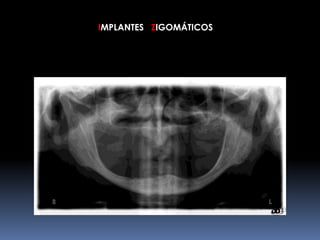

IMPLANTES ZIGOMÁTICOS     INDICAÇÕESMaxilar Edéntulo com Grande Reabsorção óssea		Pneumatização do Seio Maxilar	Status Pós-Maxilectomia	Fenda Lábio-Palatina

IMPLANTES ZIGOMÁTICOSFRACASSO FACIALHipoplasia maxilarFalso prognatismo